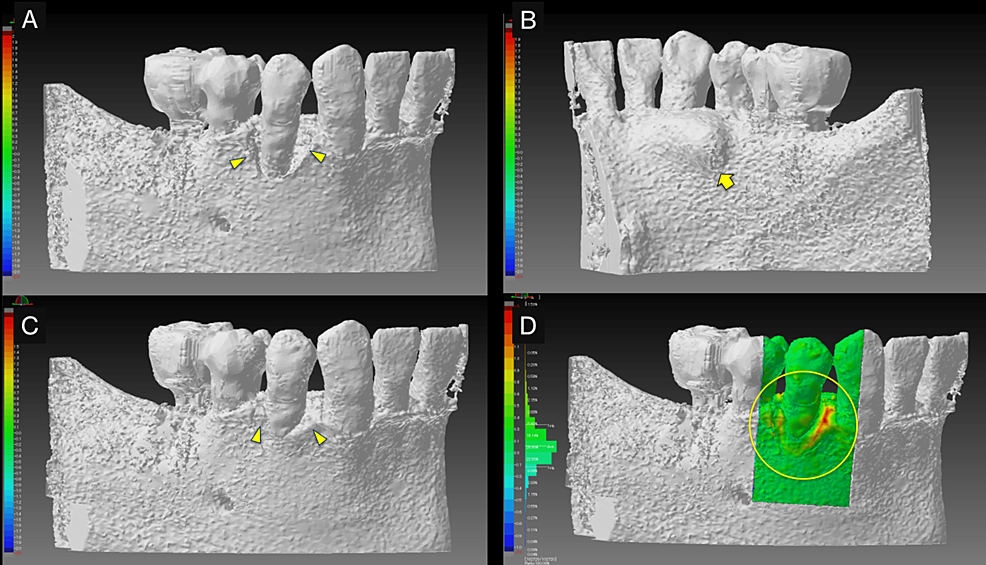

Intraoral radiography and CBCT scanning were performed 14 months postoperatively (Figures 4, 5). The results were displayed on a personal computer monitor screen, and the morphology of the bone at the surgical site and its internal structure was observed in 3D, by which the regrowth of bone-like structures at the site of the intrabony defect was confirmed. At two years postoperatively, no subjective symptoms such as pain or objective signs such as tooth movement or gingival recession were observed. No other notable findings or abnormalities were observed, and the postoperative course was judged to be good.

In teaching a clinical case, it is necessary to clarify the treatment goals. Therefore, polygonal mesh models were created from superimposed pre- and postoperative CBCT images to allow 3D observation of therapeutic changes during periodontal tissue regeneration (Figure 6). The 3D computer-aided design (CAD) inspection software package “SpGauge 2014.1” (Armonicos, Shizuoka, Japan) was used to display dimensional errors on a color map.